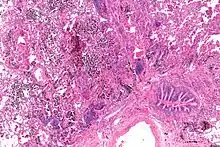

| Micrograph showing a pulmonary hemorrhage. H&E stain. | |

Pulmonary hemorrhage (or pulmonary haemorrhage) is an acute bleeding from the lung, from the upper respiratory tract and the trachea, and the pulmonary alveoli. When evident clinically, the condition is usually massive.[1] The onset of pulmonary hemorrhage is characterized by a cough productive of blood (hemoptysis) and worsening of oxygenation leading to cyanosis.[1] Treatment should be immediate and should include tracheal suction, oxygen, positive pressure ventilation, and correction of underlying abnormalities such as disorders of coagulation. A blood transfusion may be necessary.[1]